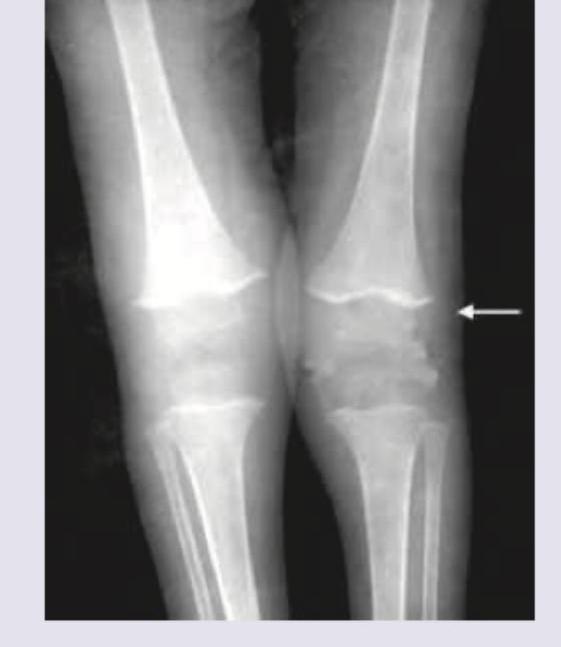

The X-ray of the patient shows?

Explanation: ***Scurvy*** - The X-ray images display classical findings of scurvy, including a **dense metaphyseal line** (white line of Frankel), **lucent zone beneath the metaphysis** (Trümmerfeld zone), and **epiphyseal separation** due to capillary fragility. - The findings are particularly evident at the distal ends of the femur and proximal tibia, consistent with **subperiosteal hemorrhages** and impaired osteoid formation characteristic of **vitamin C deficiency**. *Rickets* - Rickets is characterized by **widening, cupping, and fraying of the metaphyses**, often accompanied by **growth plate widening** and bowing of long bones due to defective mineralization of bone matrix. - These features are not the predominant findings in the provided X-rays, which show distinct abnormalities related to hemorrhage and bone fragility. *Hemarthrosis* - Hemarthrosis refers to bleeding into a joint space, often characterized by **joint effusions** and possibly **bone erosions** if chronic, typically seen in conditions like hemophilia. - While subperiosteal hemorrhages are present in scurvy, the X-ray findings are broader than just intra-articular bleeding and include specific metaphyseal changes. *Sun burst appearance* - A "sunburst appearance" is a classic radiographic finding often associated with aggressive **bone tumors** like **osteosarcoma**, indicating **spiculated periosteal reaction** extending perpendicularly from the bone cortex. - This pattern is absent in the provided X-rays, which show signs of metabolic bone disease rather than a primary bone tumor.